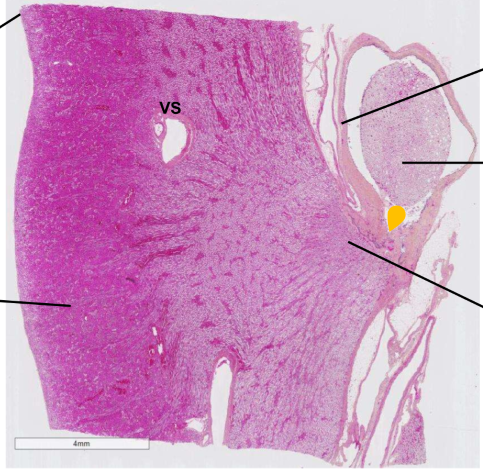

A

lame de rein HES

• capsule (tissu conjonctif)

• cortex (plus foncé, contient corpuscule rénale, tube contourné, tube collecteur)

• calice (fait d’urothélium)

• artéfact (une autre partie du rein dans le calice)

• Médullaire (plus pale, contient tube collecteur, Anse de henle, vasa recta)

Truc***

Beaucoup plus clair vers la medullaire

Elle forme une pointe vers le calice